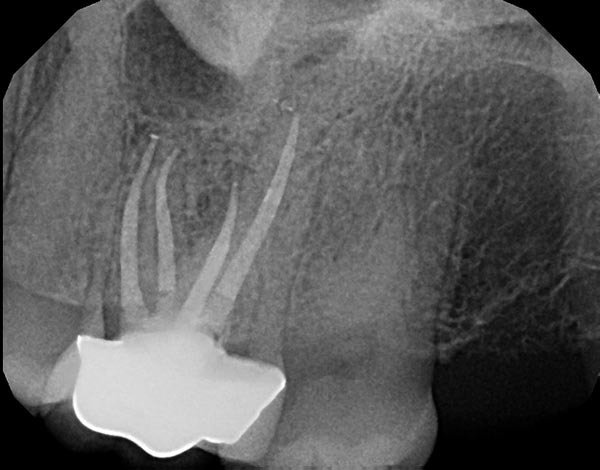

Fig. 3a: Preoperative image of tooth #3 with a necrotic pulp. The MB root illustrates a significant curvature in the apical half of the root, suggesting a highly flexible file as the best alternative. Fig. 3b: The FlexAccess file from Dentsply Sirona was used because of its ability to shape canals efficiently, but mostly because of its extreme flexibility. Fig. 3c: The postoperative image shows the files were able to follow the natural curves of the canal in multiple planes as the MB and ML canals joined in the apical half of the root.

Fig. 3a

Fig. 3b

Fig. 3c

Historically, an “unwind” may be the first step in the failure of an endodontic file. Manufacturers have engineered extremely cyclic fatigue-resistant files that unwind and have very limited cutting efficiency. These files don’t break, but they also don’t have the ability to cut dentin or follow the natural canal anatomy. In this scenario, there is added chair time and additional cost for every deformed file that needs to be switched out for a new one. More recently this historical paradigm is no longer true, with the addition of a new file that will unwind but maintains its cutting efficiency and touts unmatched flexibility. There is no change in the file length as it unwinds and it has an extremely high resistance to cyclic fatigue. As a result, this file hits three of the four corners of the ideal file from Fig. 1. Although it lacks torque strength, the unwinding doesn’t decrease the functionality of the file (Fig. 3b).